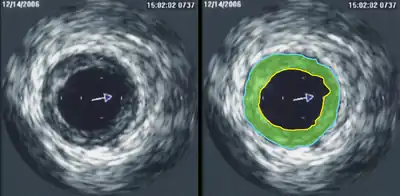

Intravascular ultrasound

Intravascular ultrasound (IVUS) is a specialized form of echocardiography that uses a catheter to insert the ultrasound probe inside blood vessels. This is commonly used to measure the size of blood vessels and to measure the internal diameter of the blood vessel. For example, this can be used in a coronary angiogram to assess the narrowing of the coronary artery. If the catheter is retraced in a controlled manner, then an internal map can be generated to see the contour of the vessel and its branches.